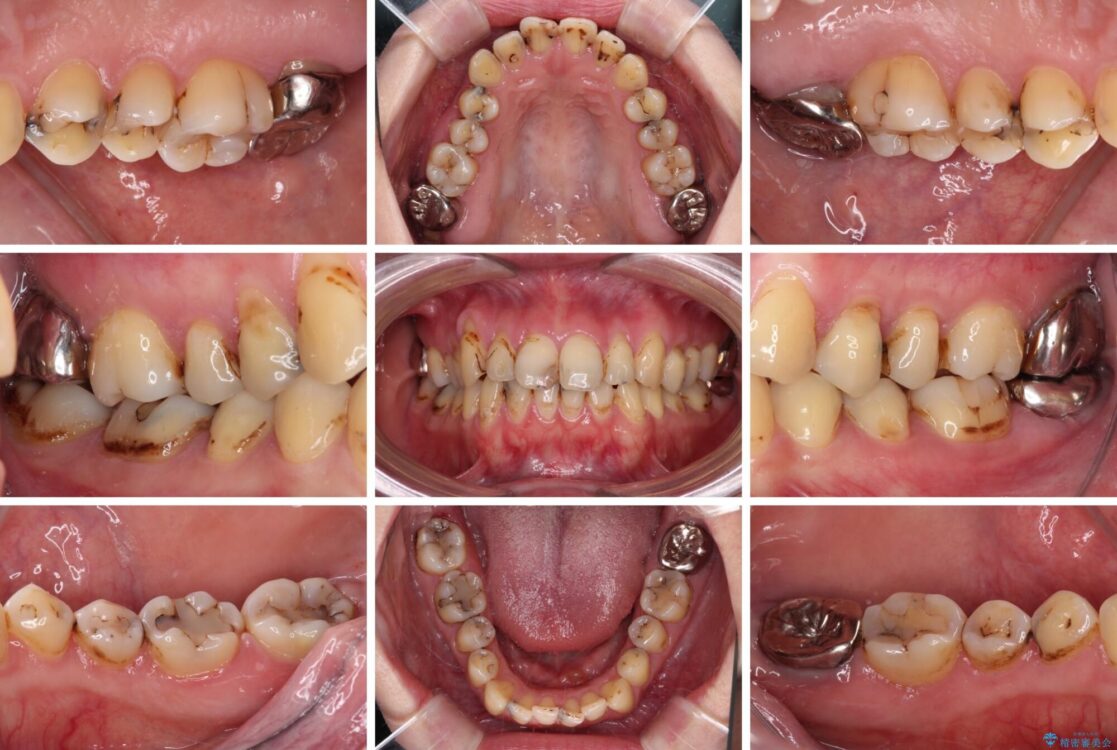

上下前歯や奥歯の虫歯治療を希望して来院された患者様です。

全顎的にむし歯が多く、根管治療の必要な奥歯や、審美的に気になっている前歯を中心にオールセラミッククラウンにて補綴治療を行うこととしました。

上顎前歯は歯肉退縮により歯根が露出していたため、事前に歯肉移植術により根面被覆を行い、その後にオールセラミッククラウンを装着することとしました。

治療前

• むし歯だらけの前歯をオールセラミッククラウンできれいに 治療前画像